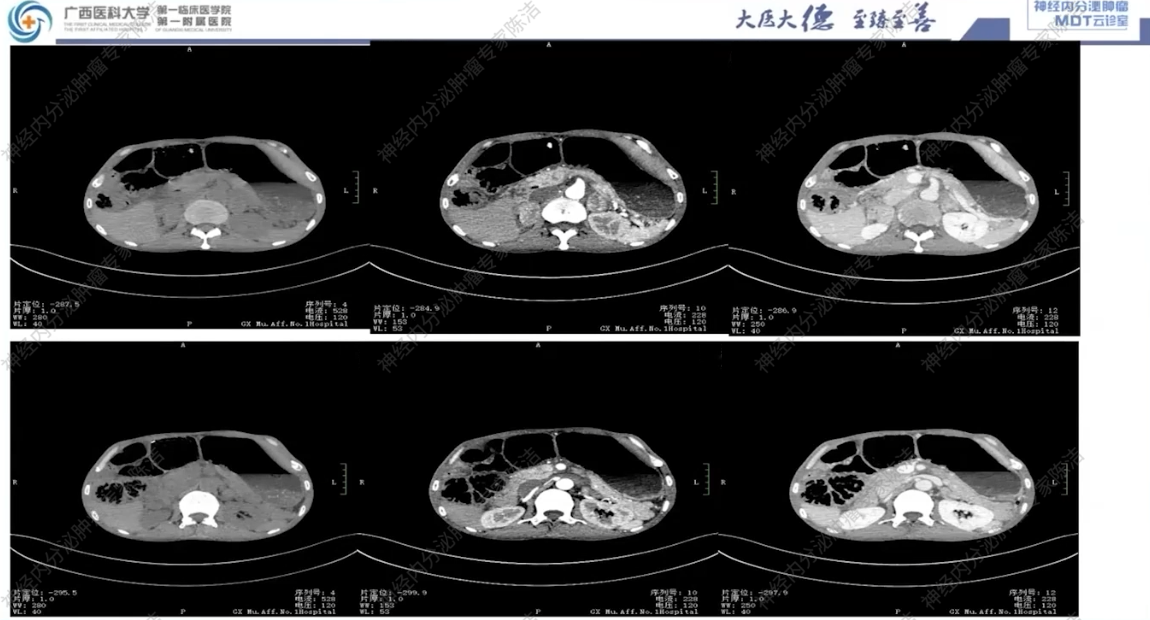

2021年12月13日,当地县人民医院就诊:CT检查提示:1.腹主动脉CTA未见明显异常;2.两侧肾上腺占位,结合临床首先考虑肾上腺髓质来源病变,嗜铬细胞瘤可能性大,未能除外肾上腺转移瘤及肾上腺皮质癌;3.腹膜后小淋巴结,4.十二指肠壁轻度增厚,拟炎症;结肠明显扩张、积气,5.间位结肠。

CT:双侧肾上腺占位伴双肺多发结节,考虑恶性嗜铬细胞瘤伴肺转移可能性大;同时可见双肾囊肿、肠郁张、双肺慢性炎症及肺气肿。

影像诊断科汤伟教授:影像学上,患者双肺多发结节,边界清晰,高度怀疑为转移瘤。腹部CT可见肠管明显扩张积气,呈肠梗阻样改变,符合巨结肠的表现。双侧肾上腺可见富血供的占位,符合嗜铬细胞瘤。垂体MRI平扫虽未做增强,但冠状位可见垂体左侧有低信号微腺瘤的可能,建议行垂体薄层动态增强扫描以明确诊断。